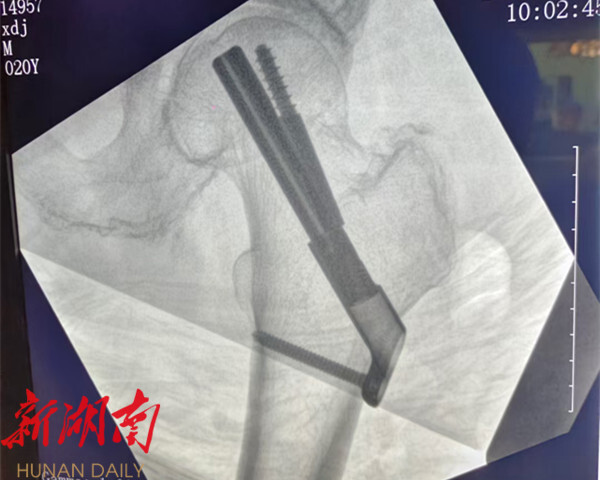

湖南日报·新湖南客户端6月5日讯(通讯员 蒋平 邓燕芳)近日,永兴县人民医院骨一科成功为一名69岁的股骨颈骨折患者许阿姨实施了闭合复位股骨颈动力交叉钉系统(FNS)内固定手术。此项技术的率先应用,不仅为患者提供了更优治疗方案,也标志着永兴县人民医院在创伤骨科微创治疗领域取得重要突破。

许阿姨因不慎摔倒导致右髋部剧痛,无法活动而入院,经医生诊断为“右股骨颈骨折”。充分考虑患者年龄与伤情,骨一科医师团队果断采用微创FNS技术,紧急为许阿姨施行保髋手术。手术过程顺利,精准复位骨折端并实现稳定固定,术中出血少,切口仅约4厘米,患者术后生命体征平稳。

相较于传统股骨颈骨折固定方式,FNS系统优势显著。

力学性能更强更稳。 其生物力学强度约为传统三枚空心钉的两倍,抗旋转能力显著优于动力髋螺钉系统,极大提升了固定后的稳定性,有助于降低骨折不愈合风险。